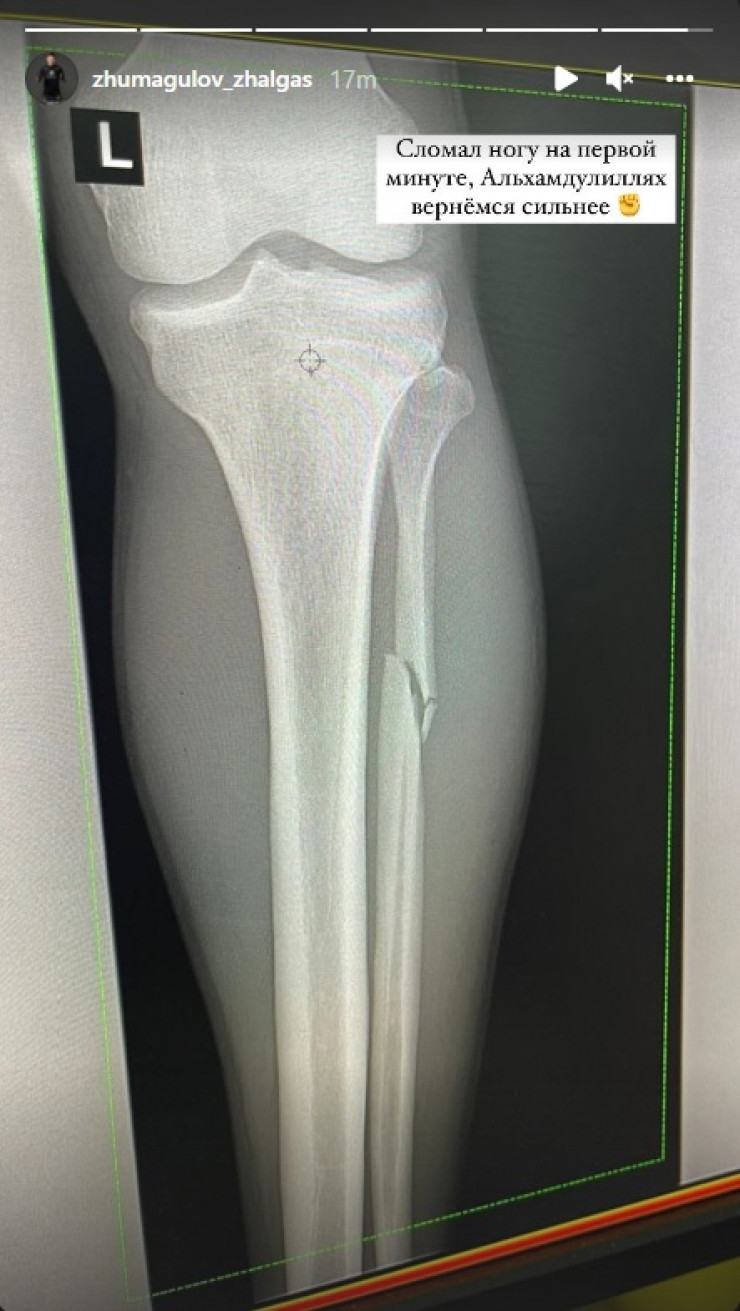

Қазақстандық аралас жекпе-жек шебері Жалғас Жұмағұлов соңғы шайқасында ангололық Манель Капеге қарсы октагонға шығып, бірінші раундта жеңіліс тапқан болатын, деп хабарлайды Egemen.kz.

Жекпе-жектен кейін қазақ спортшысының жарақат алғаны белгілі болды.

«Шайқастың бірінші минутында аяғымды сындырып алдым. Сегіз бұрышқа мұнан да күшті болып ораламын», деп жазды қазақ оғланы өзінің инстаграмдағы аккаунтында.